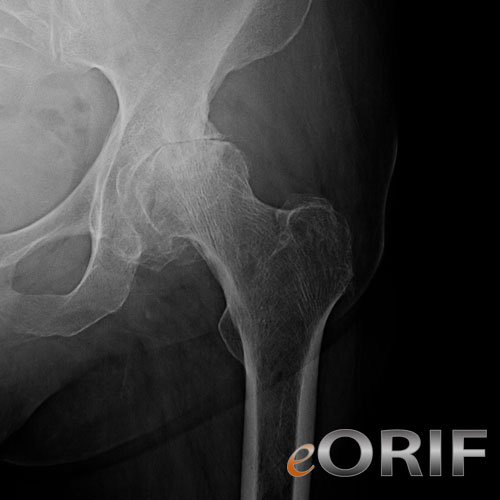

Arthritic hip xray